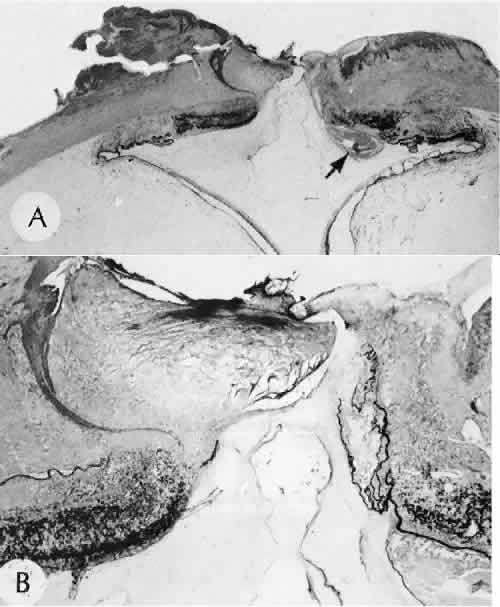

SCLERAL HEALING

The sclera itself does not participate directly in wound healing. Partial-thickness injuries are healed by formation of granulation tissue from the epi-scleral tissue in external wounds or from uveal tissue in internal wounds (Fig. 8). Full-thickness defects of the sclera heal by granulation tissue originating in the episcleral tissue and uveal tract. Mitomycin is used in filtering procedures specifically to prevent the formation of granulation tissue and promote establishment of an aqueous fistula.30

Fig. 8. Following a scleral incision, granulation tissue from episcleral tissue (E) and uveal tissue (U) will proliferate through the full extent of the sclera. The tissue will remodel along tension lines to reapproximate the tensile strength of the original tissue (Hematoxylin-eosin stain; × 28.)